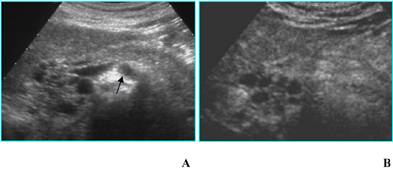

a) B-mode US can characterize a SMA when it demonstrates the typical honeycomb appearance [10,12]; CEUS, by depicting septa enhancement and the absence of papillary projections, allows a better diagnostic confidence (Fig. 5). In case of small nonsurgical lesions, CEUS doesn't need a further diagnostic step with CT and/or MR.

Fig 5

Serous microcystic adenoma in an asymptomatic 82-year-old woman. A. B-mode US shows a focal lesion located in the head of the pancreas with a honeycomb appearance. Superior mesenteric artery (arrow) is visible. B. CEUS confirms the findings of B-mode US, allowing a better diagnostic confidence.

b) Unilocular single cyst (without internal septa, solid component, parietal or central calcifications) at B-mode US can be referred to pseudocyst, oligocystic serous cystadenoma, MCN, IPMT (branch-duct type) [12]; CEUS doesn't give any additional diagnostic information (Figs. 6A and B): in particular it is not able to find out communication with the pancreatic duct that can be demonstrated by MR cholangiopancreatography or CT, especially with curved reformatted images (Figs. 6C and D), in IPMTs [13].

Fig 6

Benign mucinous cystic neoplasm in a 79 old-woman with history of abdominal pain. A. B-mode US shows a unilocular cyst 3,5 cm in diameter (asterisk), located in the uncinate process of the pancreas; main pancreatic duct, not dilated (white arrow), is visible. B. CEUS image confirms the unilocular aspect of the cyst (asterisk), without septa or mural nodules. C and D. MDCT confirms on axial image (C) the unilocular aspect of the cyst (asterisk) and on MinIP image (D) demonstrates the absence of communication with the pancreatic duct (black arrow); dilated bile duct (white arrow) is visible.